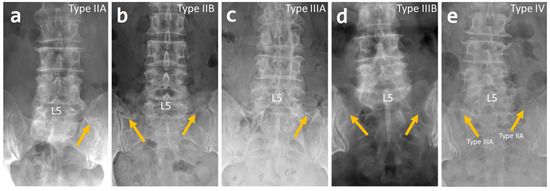

- Castellvi, A.E.; Goldstein, L.A.; Chan, D.P. Lumbosacral transitional vertebrae and their relationship with lumbar extradural defects. Spine 1984, 9, 493–495. [Google Scholar] [CrossRef] [PubMed]

| Castellvi Classification | |

| Type IIA | 46 (44%) |

| Type IIB | 17 (16%) |

| Type IIIA | 9 (8.3%) |

| Type IIIB | 30 (27.5%) |

| Type IV | 4 (3.7%) |